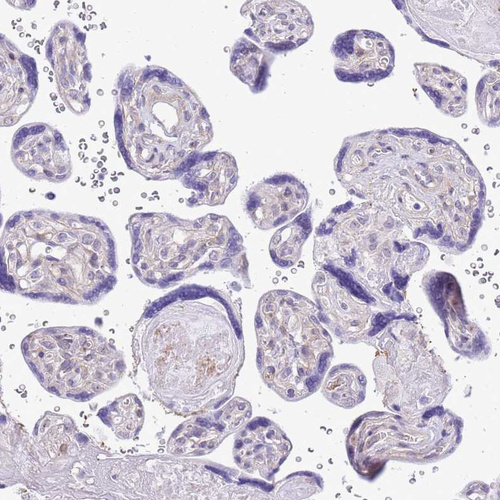

Immunohistochemical staining of human stomach shows strong cytoplasmic-membranous positivity in glandular cells.